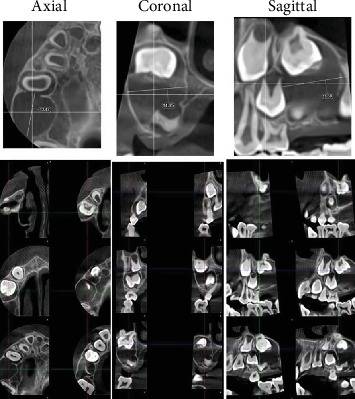

目的:本报告旨在概述罕见的囊性成釉纤维瘤,以促进其与其他牙源性病变(包括牙囊肿和囊性成釉细胞瘤)的区分。病例报告:一名8岁女孩,无明显病史,于1个月前首次发现右侧上颌无痛性肿胀,体积逐渐增大,伴颊皮质单皮质扩张。圆锥束计算机断层扫描显示右侧上颌骨后缘一清晰的单眼低密度病变,大小约为3 × 2 cm;中央骨病变涉及未出牙的第一恒磨牙。保守摘除病变核,同时拔除阻生牙。镜下检查显示良性混合囊性牙源性肿瘤,在粘液样细胞丰富的基质中显示牙源性上皮链和星状成纤维细胞。上皮细胞呈圆形至立方状,无有丝分裂活性或恶性肿瘤征象。整体组织学表现为囊性成釉纤维瘤。结论:囊性成釉纤维瘤的临床和影像学表现与牙源性囊肿相似,因其累及阻生牙。然而,这两种实体在组织学上可以明显区分,因为囊性房颤中所见的富含黏液细胞的基质中独特的牙源性上皮链在含牙囊肿中是不存在的。

Objective: This report is aimed at outlining the unusual cystic variant of ameloblastic fibroma to facilitate its demarcation from other odontogenic lesions, including dentigerous cysts and cystic ameloblastomas. Case Report: An 8-year-old girl with no significant medical history presented to the oral surgery department with a painless swelling in the right maxillary region, first noticed 1 month ago, which gradually increased in size, accompanied by monocortical expansion of the buccal cortex. Cone beam computed tomography revealed a well-demarcated unilocular low-density lesion in the right posterior maxilla, measuring approximately 3 × 2 cm; the central bony lesion involved an unerupted first permanent molar. Conservative enucleation of the lesion was performed, along with the removal of the impacted tooth. Microscopic examination showed a benign mixed cystic odontogenic tumor, displaying odontogenic epithelial strands with stellate-shaped fibroblasts in a myxoid cell-rich stroma. The epithelial cells were rounded to cuboidal, with no mitotic activity or signs of malignancy. The overall histological image suggested a cystic ameloblastic fibroma. Conclusion: Clinically and radiographically, cystic ameloblastic fibroma may resemble a dentigerous cyst due to the involvement of an impacted tooth with the lesion. However, these two entities can be clearly histologically differentiated, as the distinctive odontogenic epithelial strands in a myxoid cell-rich stroma that are seen in cystic AF will be absent in a dentigerous cyst.